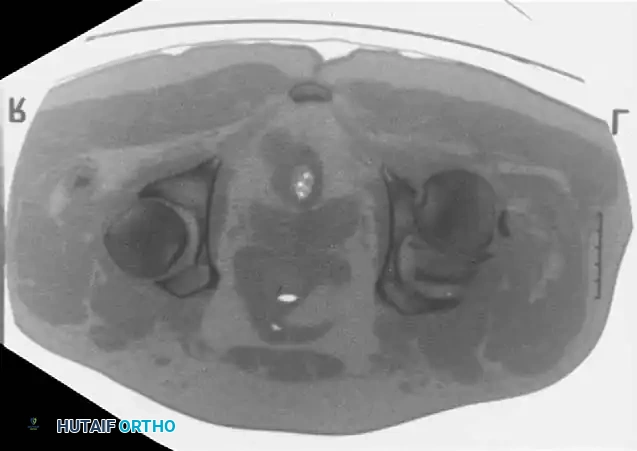

Advanced Imaging: Computed Tomography (CT)

While plain radiographs provide the foundation for classification, fine-cut CT scanning with 2D multiplanar and 3D surface-rendered reconstructions is the gold standard for modern surgical planning.

CT imaging excels at identifying:

* Intra-articular osteochondral fragments (loose bodies).

* Marginal impaction of the articular cartilage.

* The exact size and comminution of posterior wall fragments.

* The orientation of fracture lines to plan optimal screw trajectories.